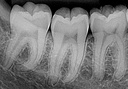

Radiografías